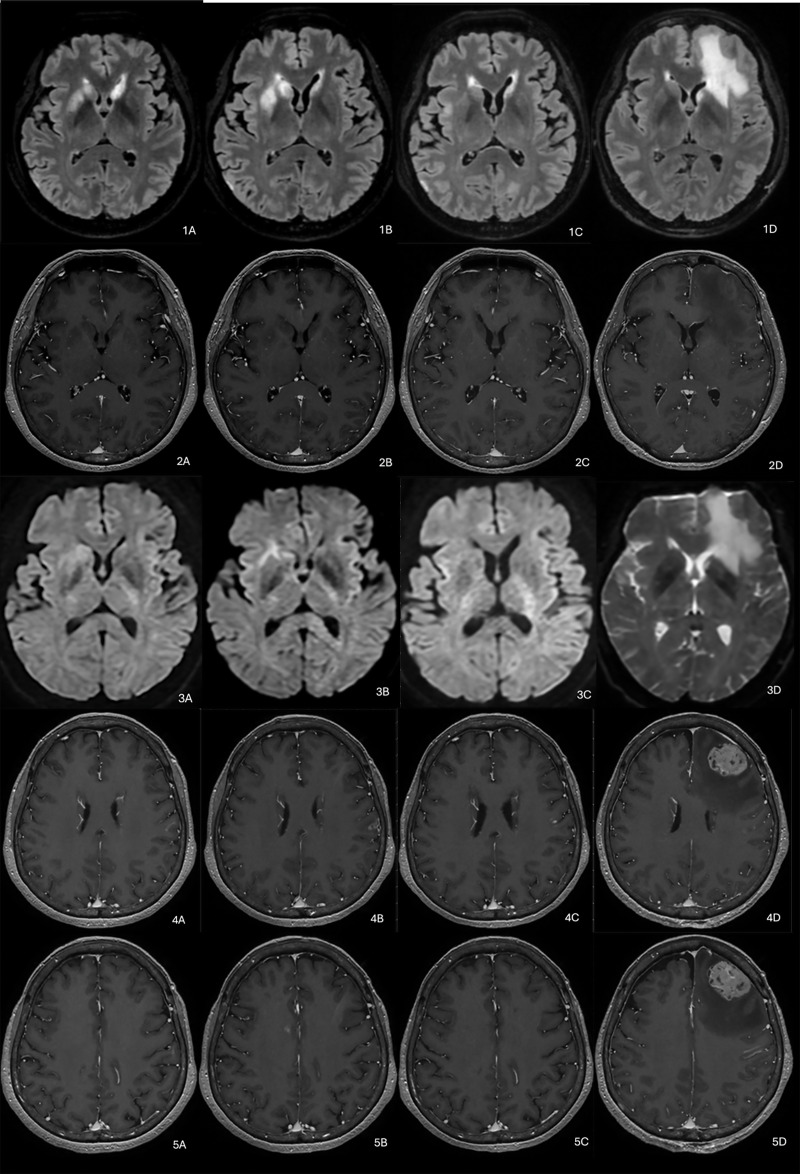

一名68岁女性,表现为进行性偏瘫和吞咽困难,最初推测为亚急性中风。连续MRI显示波动的FLAIR高强度和基底节区和皮层的强化病变,最终诊断为原发性中枢神经系统b细胞淋巴瘤。该病例强调了将临床演变与非典型神经学表现的影像学特征相结合的重要性。教学点:在FLAIR高强度波动和增强脑病变的情况下,即使没有典型的影像学特征,也应考虑原发性中枢神经系统淋巴瘤。

A 68-year-old woman presented with progressive hemiparesis and dysphagia, initially presumed to have subacute stroke. Serial MRI revealed fluctuating FLAIR hyperintensities and enhancing lesions in the basal ganglia and cortex, ultimately leading to the diagnosis of high-grade primary CNS B-cell lymphoma. The case highlights the importance of integrating clinical evolution with imaging features in atypical neurological presentations. Teaching point: In cases of fluctuating FLAIR hyperintensity and contrast-enhancing brain lesions, primary CNS lymphoma should be considered, even in the absence of typical imaging features.